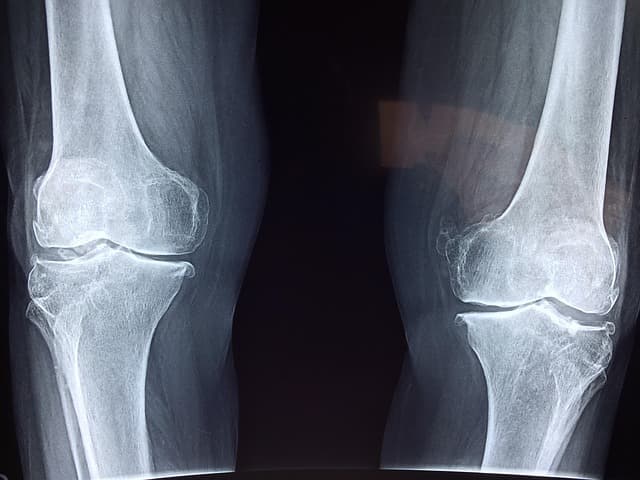

조용히 진행되는 뼈 손실은 나중에 골절이나 척추 손상, 관절 통증 등으로 나타나며, 점차 회복이 쉽지않습니다.

칼슘이 잘못된 위치에 쌓일 경우 혈관 석회화나 관절통을 겪게 됩니다.